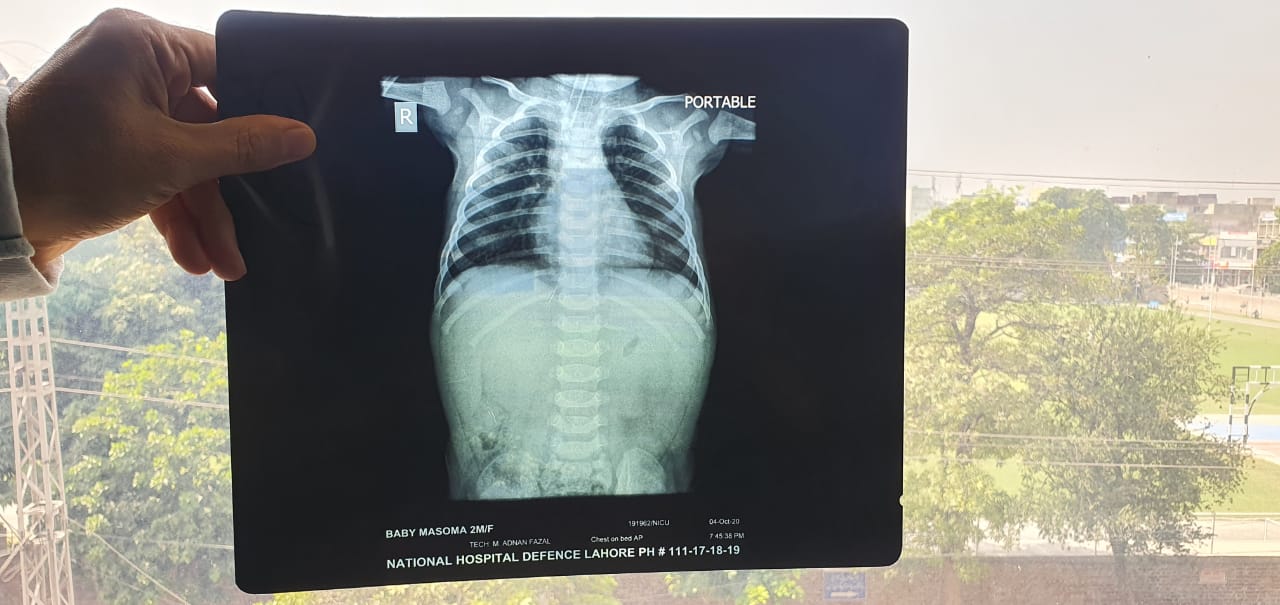

Few days back i have posted about my niece vaccine, she had her vaccine and was having bleeding for 3days after that, she went to doc and they said to just do icing. After 3 to 4days in morning she did vomit and motion, after feeding she slept as normal, but later didn't respond, they immediately took her to hospital 'isko sans lene mai prib horhe hai' doc said konsi sanz isko koi sans nahi arhe, and shifted to Icu ventilator.. Docs have no hope. We want second opinion attaching her reports kindly give your opinion asap, i have more pics but can attach only 5

kindly provide more reports and CT scan if available.

she seems to have bleeding disorder which causes prolonged bleeding and probable bleed in her brain

that made her unconcious